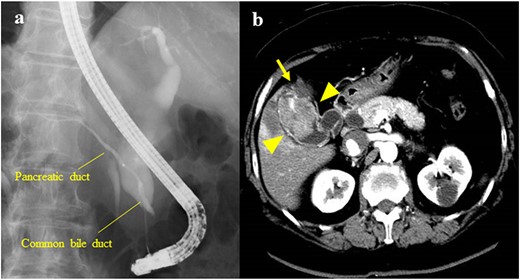

The patient was a 62-year-old man who was diagnosed with PBM with Type Ia CBD 4 years previously (Fig. 3a). On magnetic resonance cholangiopancreatography (MRCP), the largest diameter of the common bile duct was 29 mm. However, the patient refused treatment and underwent follow-up observation alone. He visited the hospital regularly and underwent serum tumor marker tests and imaging (CECT or MRCP) annually despite the absence of symptoms. Approximately, 4 years after his diagnosis, gallbladder cancer was detected on CECT, which was performed as part of the regular follow-up examination for PBM. The patient had a previous medical history of alcoholic cirrhosis (Child–Pugh B), diabetes mellitus and hypertension. Laboratory examinations revealed the following values: platelet count, 9.5 × 104/μl; aspartate transaminase, 47 U/l; gamma-glutamyltransferase, 138 U/l; total bilirubin, 1.4 mg/dl; albumin, 3.4 g/dl; prothrombin time, 65%; carcinoembryonic antigen, 10.4 ng/ml; carbohydrate antigen 19–9, <2 U/ml and duke pancreatic monoclonal antigen type 2, 570 U/ml. In the current examination, contrast-enhanced CT revealed an 11-mm mass with a contrast effect in the gallbladder despite the absence of a mass 4 years previously (Fig. 3b). The patient then underwent extrahepatic bile duct resection and cholecystectomy. The gallbladder had atrophied and had been buried in the liver (Fig. 4a and b). The amylase level in the bile samples collected from the gallbladder and common bile duct were 6590 and 15 270 U/l, respectively. A pathological examination revealed well-differentiated adenocarcinoma of the gall bladder without bile duct involvement (T1aN0M0 Stage I) (Fig. 4c). R0 resection was performed. However, the patient developed hepatic failure, refractory ascites and spontaneous bacterial peritonitis after surgery and died of sepsis after 4 months.

(a) MRCP showing PBM with Type Ia CBD; the largest diameter of the common bile duct was 29 mm; (b) CECT showing an 11-mm mass with a contrast effect in the gallbladder (arrowhead).